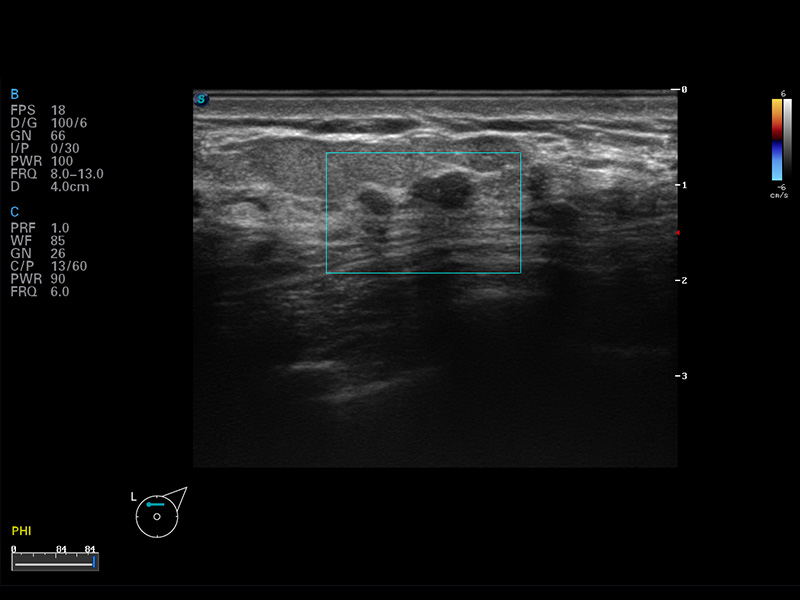

S8 EXP便携式彩色多普勒超声诊断仪是球速体育入口研发的高端全身应用型便携彩超。高通道的VIS平台融合可视化(Visual)、智能化(Intelligent)和人性化(Smart)的特点,配以球速体育入口自主研发生产的探头大家族,使您能够快速、准确的获得病人信息,提高工作效率的同时减轻疲劳。

μ-Scan微米成像

谐波成像

空间复合成像